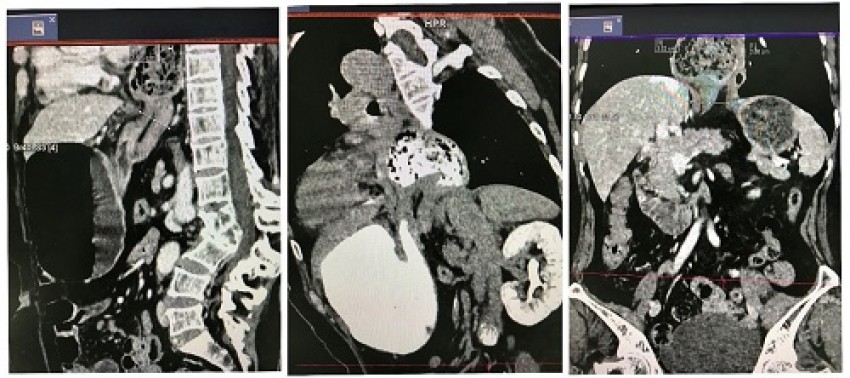

Hình ảnh thoát vị dạ dày thể hỗn hợp lên lồng ngực qua khe thực quản.

Chụp cắt lớp vi tính và chụp cắt lớp có tiêm kết hợp uống thuốc cản quang hiện nay được áp dụng khá phổ biến trong chẩn đoán TVH. Đặc biệt TVH ở người lớn. Qua hình ảnh thu được từ các lát cắt sẽ cho đánh giá chi tiết về thoát vị như vị trí thoát vị, tạng thoát vị, loại thoát vị,... góp phần tích cực trong định hướng phương pháp xử trí sau này cho bệnh nhân.